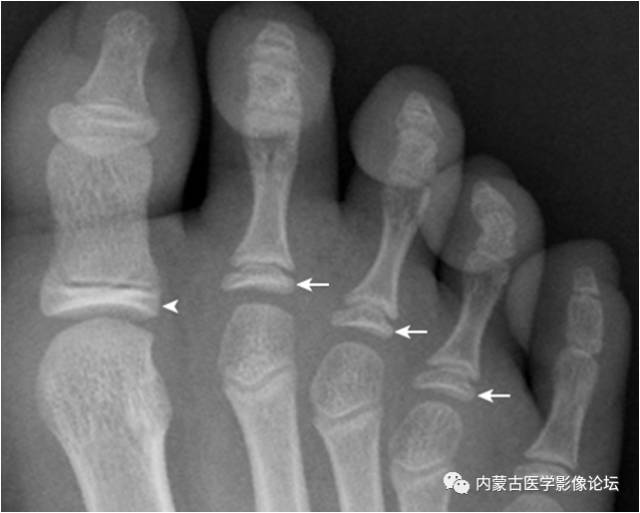

23.锥状骨骺:第2~4近节趾骨骨骺呈锥状(箭),多由生长紊乱引起,是一种变异。同时可见拇趾近节趾骨骨骺密度增高(箭头)。

22.趾骨骨骺:拇趾远节趾骨骨骺内侧较外侧宽(箭),其与趾骨干骺端间距离较宽(箭头),为正常表现,勿误认为是骺离骨折。近节趾骨骨骺可呈扁平状,并密度增高,亦为正常表现,勿误认为坏死。